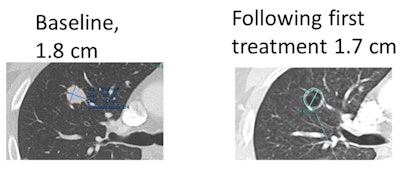

Example of metastatic lung lesion that became cavitary on the first CT following initiation of treatment. Most of the lung lesions in this patient became necrotic to the point of cavitation (commonly seen in this treatment) following the start of therapy. The lesions stayed the same size, however, and some measured larger on axial dimension. All images courtesy of Dr. Les Folio.After developing ADaVA to quantify changes in viable versus necrotic tumor volumes that are responding to antiangiogenic therapy, the researchers compared the ability of ADaVA, RECIST, and evolving criteria such as Morphology, Attenuation, Size, and Structure (MASS) and Choi. The study included 141 lesions at baseline and serial follow-up contrast-enhanced CT exams in 17 patients with metastatic bladder cancer being treated with cabozantinib, Folio said.

Folio noted that a decrease in tumor density due to necrosis shown on contrast-enhanced CT can be paired with an increase in axial size despite a qualitative response to targeted treatment. Metastatic lesions often show peripheral enhancement along with nonenhancing central components, he said.

"For example, lung lesions may cavitate and measure larger on axial slices, despite showing less volume of tissue, with live tumor remaining only in the peripheral rim," he said. "The manifestation of response is reflected in decreased density [that] is incompletely captured in RECIST, which gives us the opportunity to develop more appropriate criteria and tools for this general type of therapeutic response."